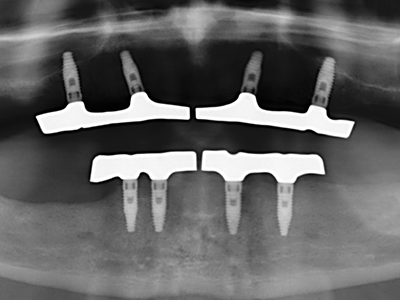

Fig. 13: Adequate irrigation with the 4-mm residual bone width is essential for this 52-year-old patient during the bone splitting.

Fig. 14: Placement of four tapered RSX implants (Bego Implant Systems, Bremen).

Fig. 15: The one-year follow-up x-ray examination shows stable conditions at the bone level.